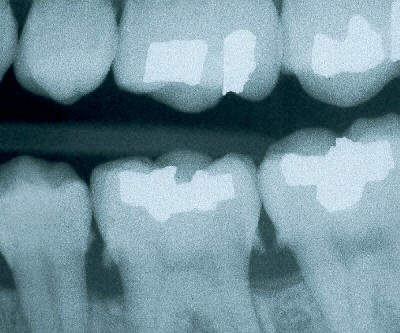

Necrotic Tooth - a tooth which has died

Though many teeth which die do NOT discolor, the dark purple area of this premolar indicates that the pulp of the tooth has died, likely due to a cavity or other trauma. Such a tooth needs root canal or other treatment in a timely manner to prevent extensive infection and abscess. Once a tooth has died, it tends to become brittle and will eventually break down without proper treatment from your dentist. Since the tooth has died, it may not feel sensitive to the patient and is often ignored. As a dentist, I routinely see patients who have broken off the entire crown of a necrotic tooth! Though the tooth may still be saved (ie- see our Cosmetic Dentistry page) after it has broken off, it may also need to be extracted.